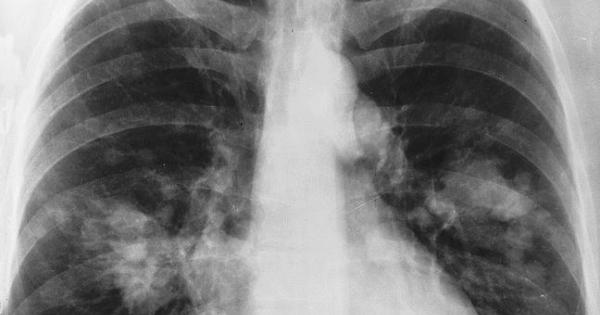

Soltanto sei secondi per accertare, con gli strumenti diagnostici più avanzati come la Tac Spirale a basso dosaggio, le condizioni in cui versano i propri polmoni, per individuare con una diagnosi precoce un tumore, riducendone la mortalità anche fino al 20%. E' questo l'obiettivo di 'Un Respiro per la Vita', campagna di diagnosi precoce giunta alla terza edizione e promossa dal Policlinico Universitario Campus Bio-Medico, rivolta a fumatori o ex-fumatori di almeno 15 sigarette al giorno con età non inferiore a 55 anni. Nei mesi di dicembre e gennaio, il Campus Bio-Medico metterà a disposizione gratuitamente 28 indagini con TAC Spirale a basso dosaggio a settimana, che permettono di "scannerizzare" i polmoni, ottenendo immagini dettagliate e riducendo allo stesso tempo l&rsquoesposizione alle radiazioni ionizzanti rispetto ad altre tecnologie. L'esame verrà affiancato, nella medesima giornata, dalla visita specialistica del chirurgo toracico, nell'ambito della quale sarà consegnato il referto, con l'indicazione di come approfondire, se necessario, l'iter diagnostico. È possibile prenotare chiamando il numero telefonico dedicato 06.225411460, attivo dal lunedì al venerdì dalle ore 9.30 alle 12.30 e dalle 13.30 alle 15.30."La diagnosi precoce &ndash spiega il dottor Pierfilippo Crucitti, coordinatore dell&rsquoiniziativa &ndash è essenziale per individuare eventuali formazioni neoplastiche quando hanno ancora dimensioni inferiori ai 5 millimetri di diametro e risultano, dunque, più facilmente "